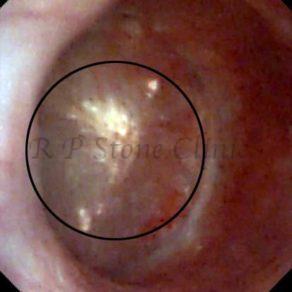

Kidney stone is a solid mass of CRYSTALS. It is the process of crystallization which initiates the formation of kidney stones. This happens in nephrons or units of kidney. Once a small crystal is formed, it can both grow & unite with other crystals leading to the formation of small concretion which eventually forms a stone. Once these large crystals detach from the collecting ducts, the process of stone formation starts in the renal collecting system. A recurrent kidney stone former is advised to know a little bit about something known as Randall’s plaque. Alexander Randall discovered plaques on the renal papillae eight decades back based on examination of 1154 pairs of autopsied Kidneys. He described these renal papillary lesions as cream colored or milk patch areas composed of calcium phosphate & calcium carbonate. These plaques could act as NIDUS for formation of KIDNEY STONE. Calcium Oxalate stone can form on this nidus & then detaches from this plaque to become a free floating stone in the collecting system of kidney

These images are taken as snap shots from the video recording of RIRS Surgery done at our hospital. These are Randall’s Plaques seen with Digital FLEX XC & Digital FLEX XC S. The cream or whitish patches are seen on the tips of RENAL PAPILLAE as seen in images below.

Randall’s Plaques may lead to the formation of Stones.

Those kidney stone patients who have Randall’s Plaques in their kidneys are more likely to form stones again (Recurrent Stones).

Stone Patients in whom Randall’s Plaques are detected at the time of RIRS Surgery should undergo regular ultrasound examination for early detection of stones.

Patients of Stones with Randall’s Plaques in their Kidneys should drink plenty of fluids in addition to Orange Juice & Lemonade.